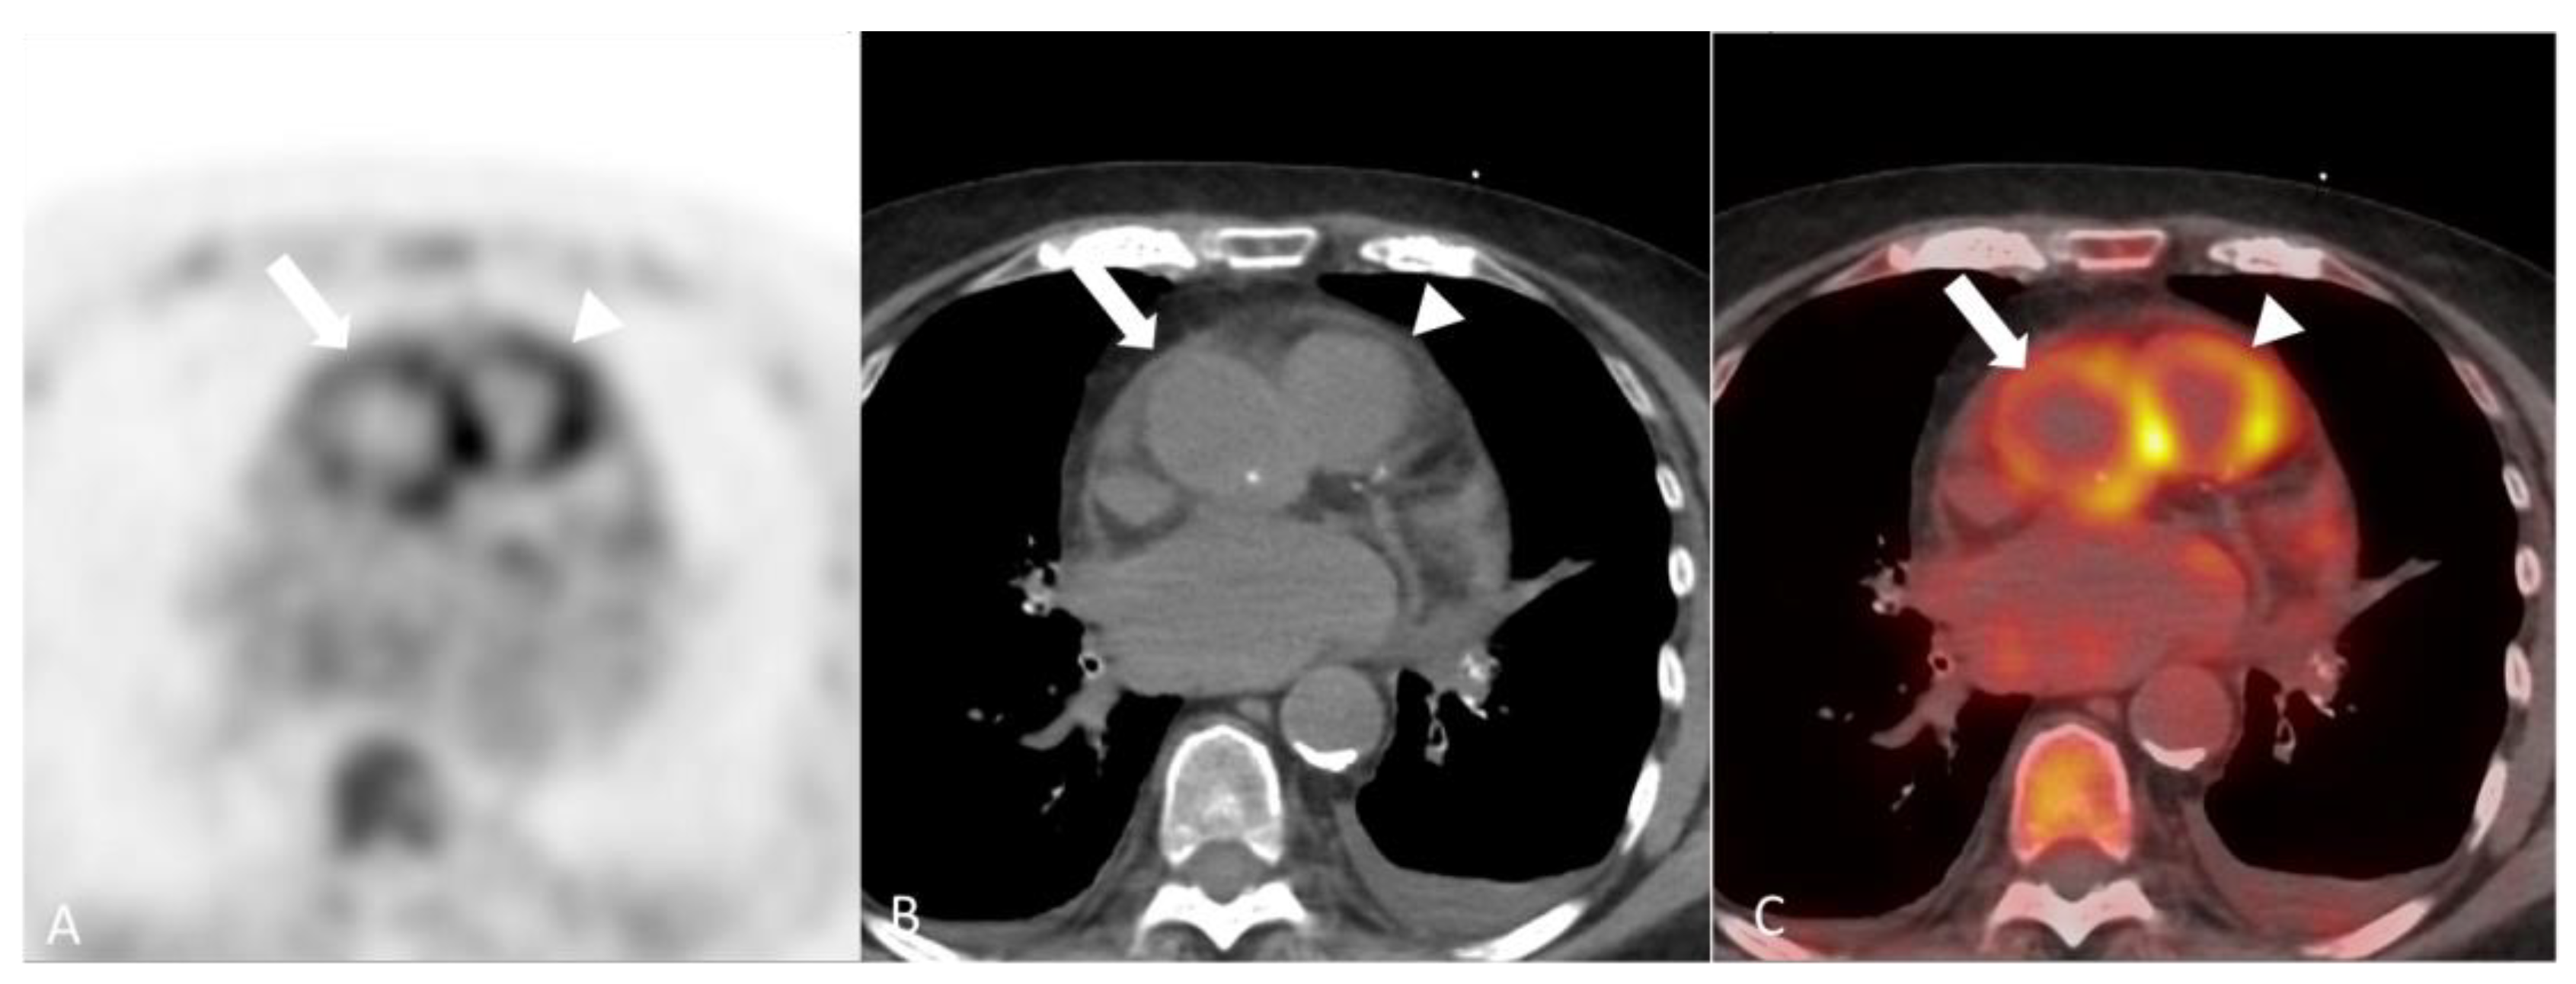

2.3.2. Eosinophilic Granulomatosis with Polyangiitis

2.4. Miscellaneous

2.4.1. Behçet’s Disease